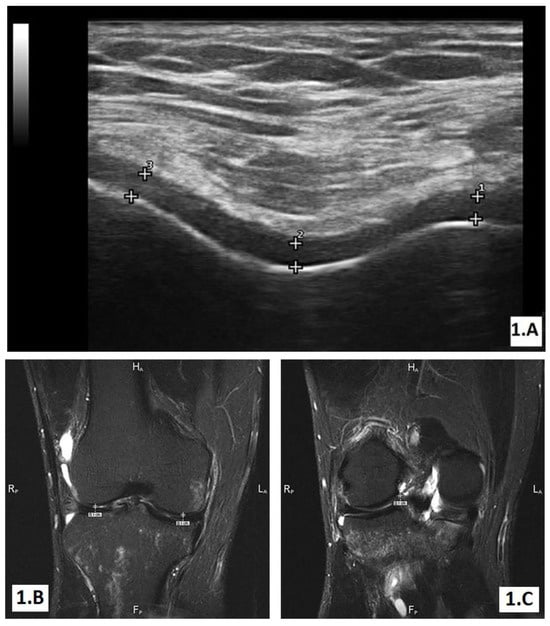

The ultrasound (US) evaluation

The MRI examination

Imaging evaluation of treatment response after 1 year